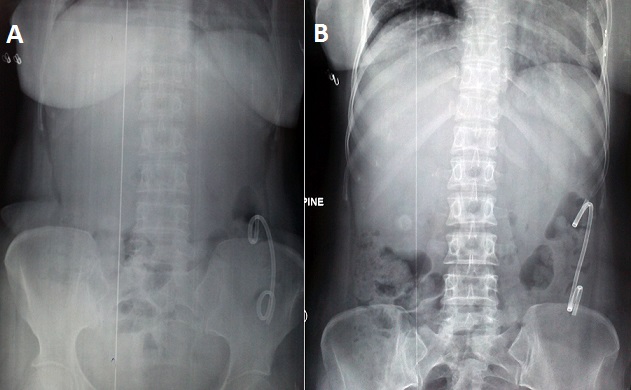

A 48 year old female presented to causality with high grade fever with rigors and chills, right upper abdominal pain and jaundice of one day duration. She had a past history of similar episode one month back for which she had undergone endoscopic biliary drainage. Hemogram revealed leucocytosis with polymorphonuclear cell predominance. Liver function tests; total bilirubin 8.4mg/dl, direct bilirubin 4.9mg/dl, alanine aminotransferase 96 U/L, aspartate aminotransferase 84 U/L, alkaline phosphatase 438 U/L and normal albumin 4.1gm/dl. Serum electrolytes and renal function tests were within normal limits. Plain x-ray abdomen revealed a radio-opaque foreign body in the left side of abdomen. Ultrasound abdomen revealed a mildly enlarged liver with dilated intrahepatic biliary tree, multiple gall stones and a dilated common bile duct. A provisional diagnosis of distally migrated double pigtailed biliary stent and cholangitis was made. Patient was managed with urgent endoscopic retrograde cholangio-pancreatography with stenting and started on parenteral antibiotics as well as other supportive measures. On the second day of admission stent passed off with fecal matter and repeat abdominal x-ray revealed no foreign body in the colon. Patient improved with treatment and is being planned for cholecystectomy. Stent migration is one of the complications of biliary stenting. Distal migration is more common than proximal migration. Risk of migration is more for plastic (5-10%) and covered metallic stents (3-12%) compared to uncovered metallic stents (<1%). Complications of stent migration include recurrence of cholangitis, pancreatitis and rarely intestinal obstruction or perforation. Stent modifications like creation of pig tails (single or double) or side flaps have been tried to reduce the risk of stent migration but with limited success. With the improvements in endoscopic techniques and expertise biliary stenting is more frequently done in the setting of acute cholangitis. Distally migrated stents may be identified as an intra-abdominal foreign body before it passes off in the stool. We hope this clinical image will introduce the primary care physicians to the radiological appearance in a case of distally migrated double pig tailed biliary stent.